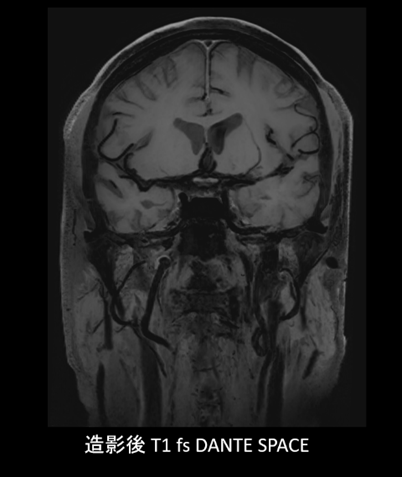

●動脈硬化性病変のリスク評価や,脳卒中再発リスクの層別化に貢献する DANTE 血液信号抑制技術(XB10より新たに搭載)

流れている血液の信号を選択的に抑制するためのRFパルス技術DANTE(Delay Alternating with Nutation for Tailored Excitation)は,流動血液信号を選択的に抑制する血液信号抑制技術。これにより,近年注目されている血管壁イメージングにおいて,血管内腔の血液信号を効果的に抑え,プラーク性状や血管壁肥厚の描出能を向上させる。動脈硬化性病変のリスク評価や,脳卒中再発リスクの層別化に貢献する。